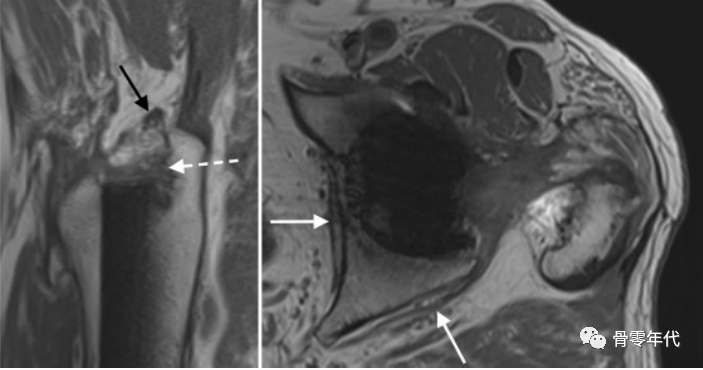

71岁女性臀小肌腱部分厚度撕裂(a和b中的箭头):(a)脂肪饱和冠状质子密度加权图像和(b)轴位T2加权脂肪饱和图像,伴有明显增厚和相关的小粗隆滑囊炎(b,虚线箭头)。(c)臀小肌腱在矢状位T1加权像上信号强度增加(星号)反映潜在的肌腱病变。